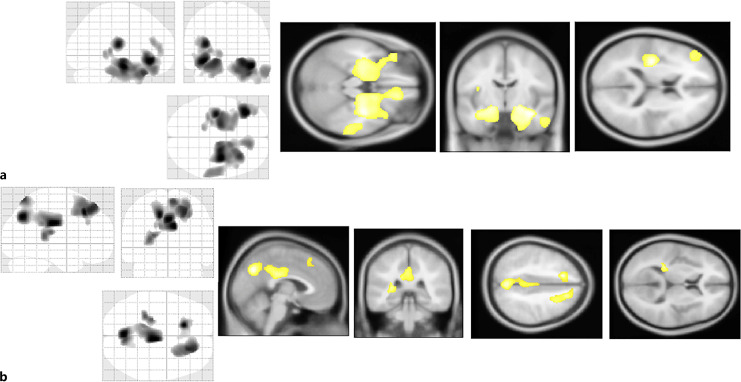

Results: Compared to the EOAD group, the LOAD group had significantly higher scores on orientation in place. Compared to the LOMCI patients, the EOMCI patients achieved significantly higher recall scores. The LOAD and LOMC groups showed significant volume reductions in bilateral medial temporal regions compared to the HCs. The EOAD and EOMCI groups did not show significant atrophy of the medial temporal region compared to the HC group.

Conclusions: The hippocampal volume and memory were preserved in the patients with EOMCI or EOAD compared to those with LOMCI or LOAD. These findings may indicate that the distinct and differing patterns of neuropsychological changes between EOAD and LOAD are also common in MCI, which is intermediate between normal cognition and AD.